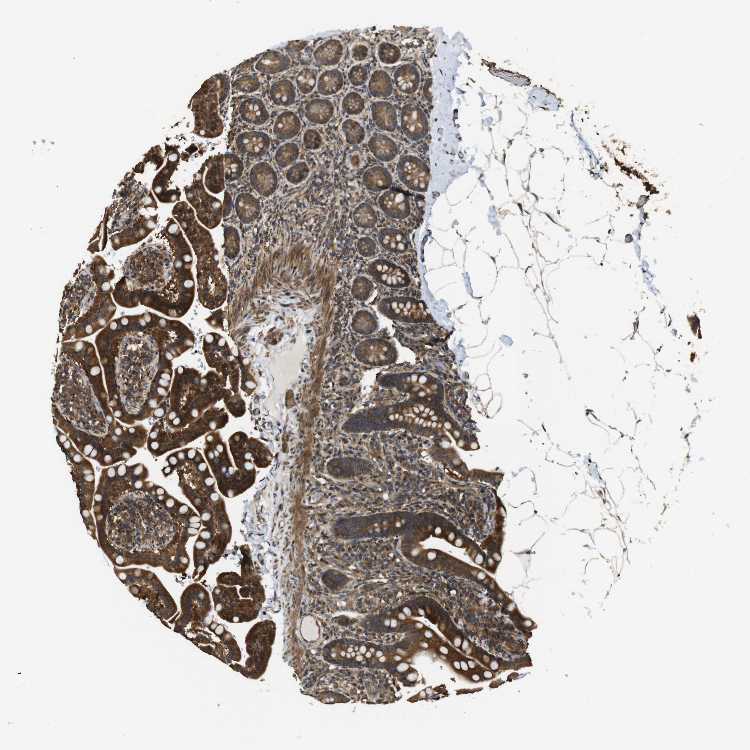

SMALL INTESTINE - Antibody stainingi

Antibody staining in the annotated cell types in the current human tissue is reported as not detected, low, medium, or high, based on conventional immunohistochemistry profiling in selected tissues. This score is based on the combination of the staining intensity and fraction of stained cells.

Each image is clickable and will lead to virtual microscopy that enables deeper exploration of all samples and also displays staining intensity scores, fraction scores and subcellular localization as well as patient and tissue information for each sample.

Antibody CAB010494

Glandular cells High